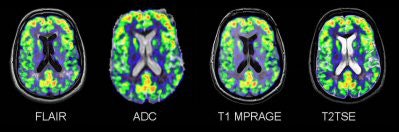

![]() |

| Brain PET and Siemens' Magnetom Trio MRI feature a removable PET head insert. Image courtesy of Siemens Medical Solutions. |